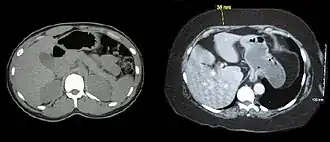

Grasa subcutánea

La grasa subcutánea es la capa de tejido subcutáneo que se distribuye más ampliamente. Está compuesto por adipocitos, que se agrupan en lóbulos separados por tejido conectivo. El número de adipocitos varía entre las distintas zonas del cuerpo, mientras que su tamaño varía según el estado nutricional del cuerpo.[9] Actúa como acolchado y como reserva de energía, además de proporcionar una pequeña termorregulación a través del aislamiento.[7] La grasa subcutánea se encuentra justo debajo de la piel, a diferencia de la grasa visceral, que se encuentra en la cavidad peritoneal, y se puede medir con calibradores de grasa corporal para dar una estimación aproximada de la adiposidad corporal total.[10]